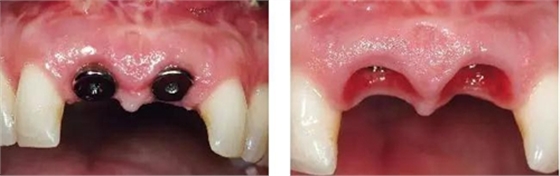

圖9、種植體植入5個月:種植體到唇側(cè)骨板的距離仍然大于2mm,這對于形成長期穩(wěn)的美學(xué)效果有很重要的作用。

圖10、剛植入種植體當(dāng)天的情況(左)和植入種植體1年時的情況(右)。

圖1、外形較大的雙側(cè)上中切牙唇側(cè)有瘺管,預(yù)后不佳,患者高笑線、薄齦生物型。

圖2、放射線片顯示雙側(cè)中切牙根尖均有感染病變。

圖3、微創(chuàng)小心拔除雙側(cè)中切牙,保護牙齦緣和齦乳頭不受損傷。

圖8、植入2顆Camlog平行壁螺紋種植體,扭矩達35Ncm。安放兩個粗直徑的愈合帽,防止軟組織退縮和凹陷。

圖11、穿黏膜愈合1周后,牙齦外形良好。

圖12、種植體植入后2個月取出愈合帽,可見牙齦外形和齦乳頭維持得相當(dāng)好。